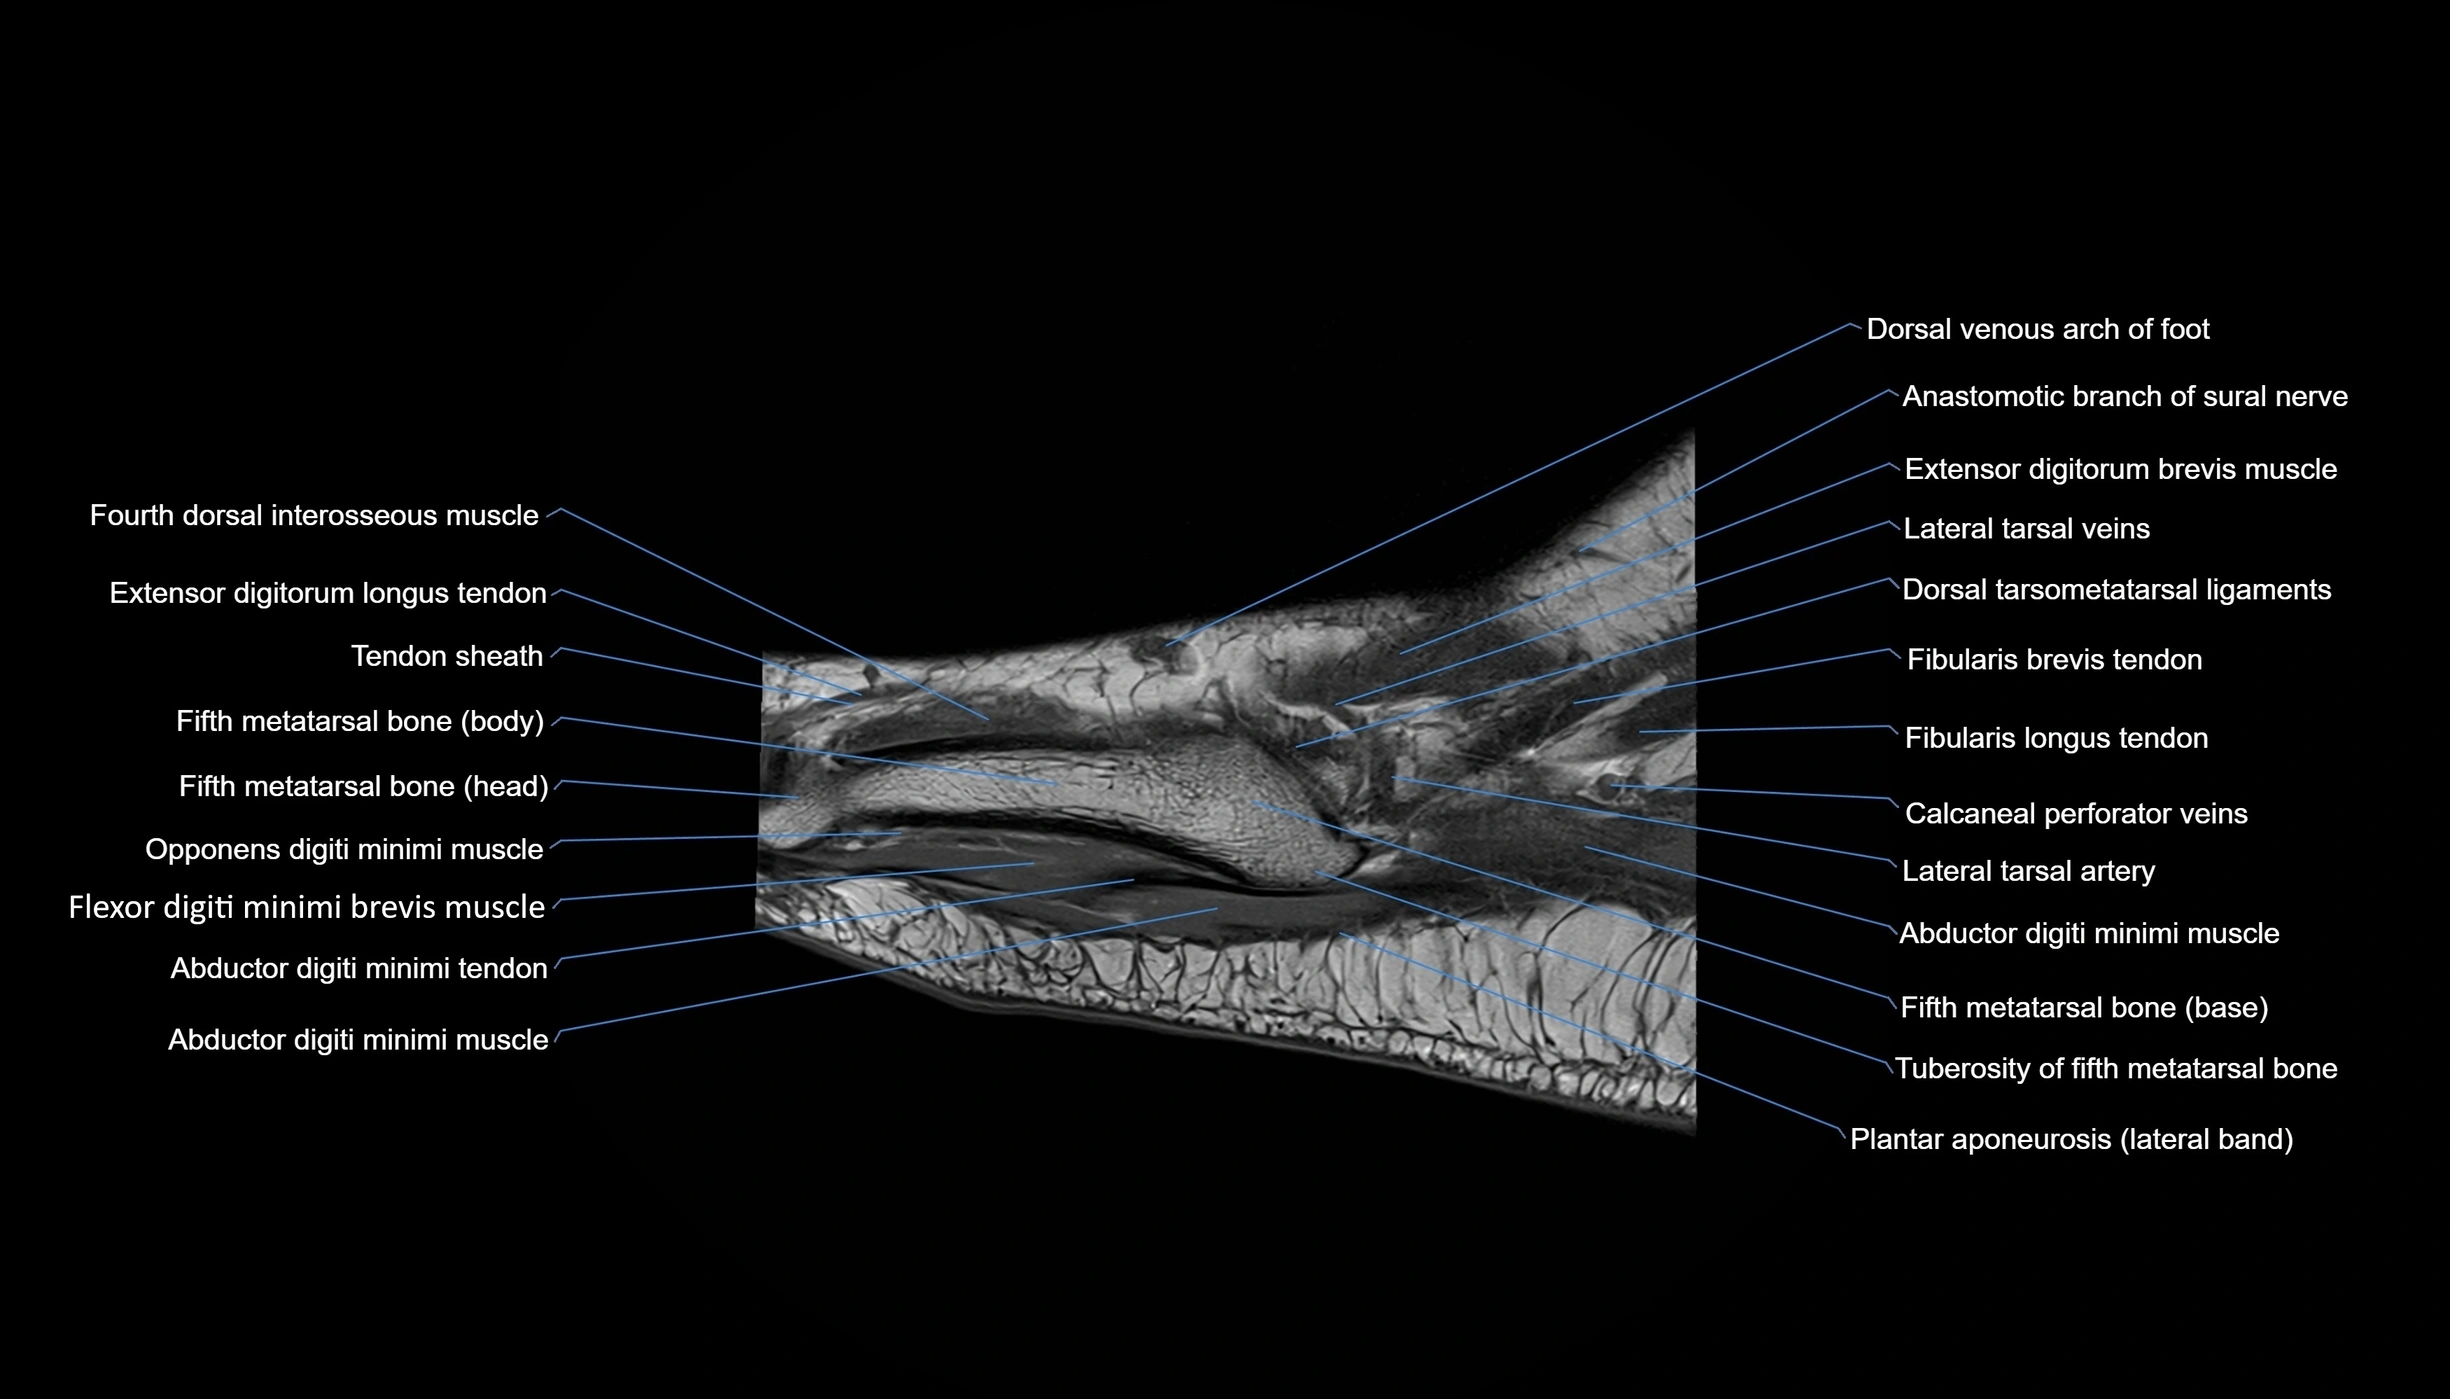

MRI image